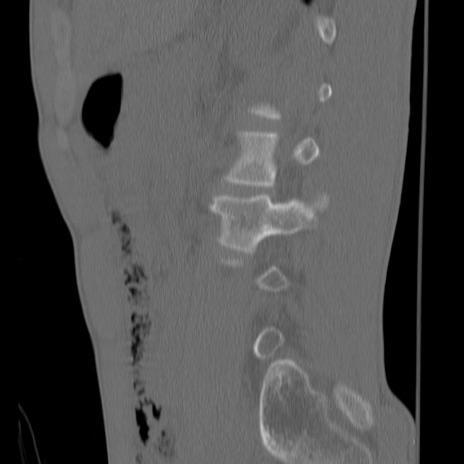

症例3 腰椎CT(矢状断像)

腰椎CT

3D再構成